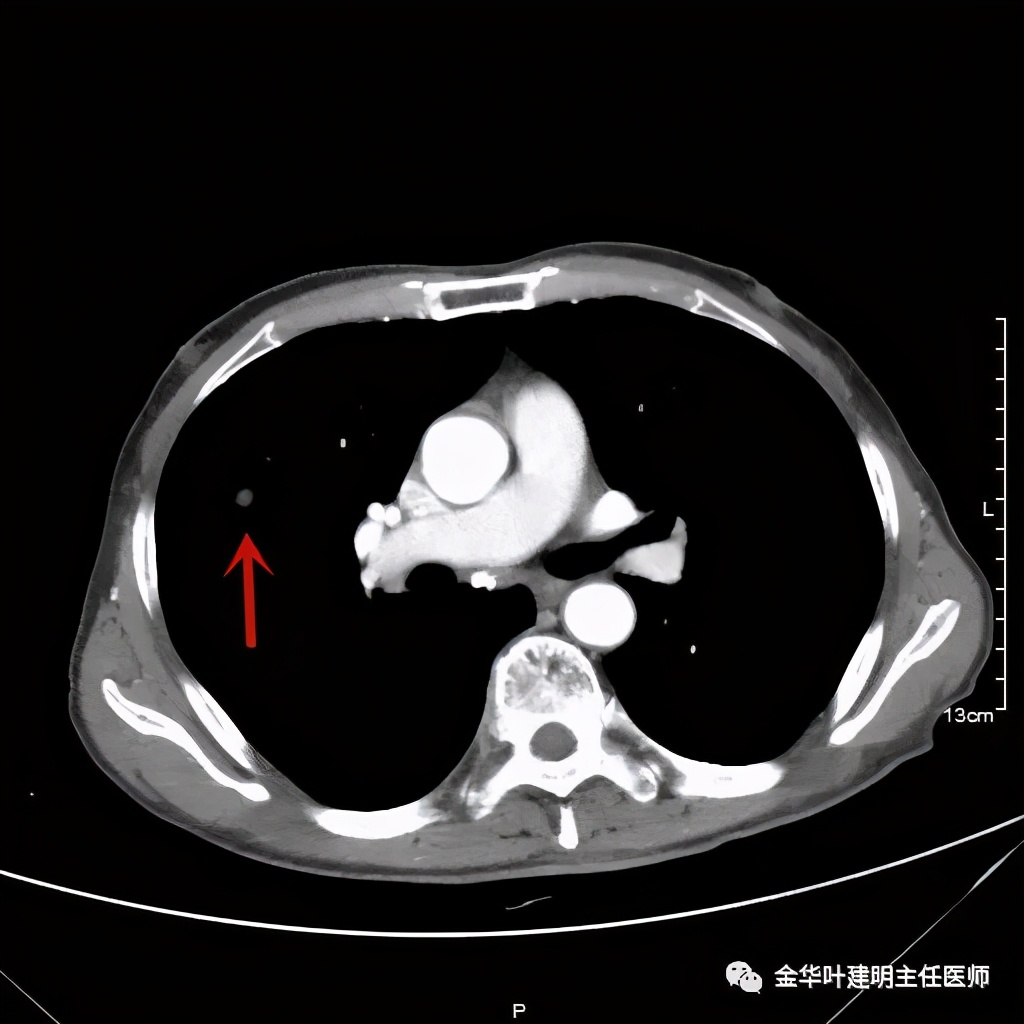

金华的某A,今年73岁,男性。检查发现右上肺占位,肿瘤筛查指标正常,血常规与CRP正常,临床有反复咳嗽、咳痰2年余(考虑慢支的关系,近期也许同时有病灶的影响)。一年前还在外院做过支气管镜,也未见确切异常。我们先来看他这次的胸部CT图像:

上图示病灶

上图示病灶快要消失的层面